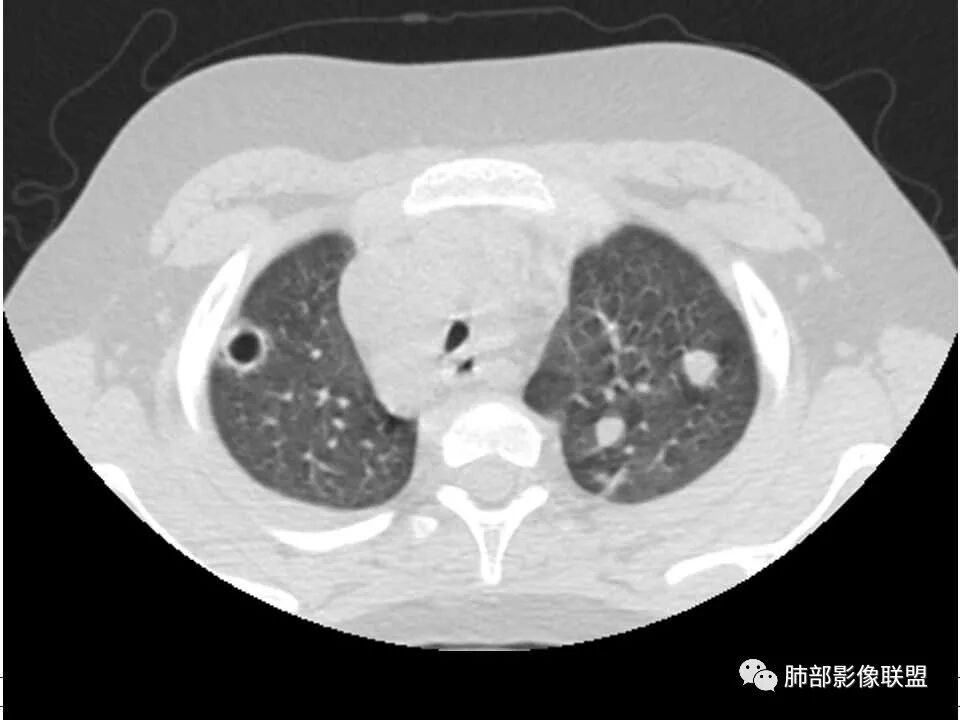

患者儿童,因右下肢疼痛伴肿胀14天就诊。病程中有发热及伴随症状。膝关节MRI提示右侧膝关节及右髌骨髁异常信号影,右膝髌上囊及关节腔内少量积液。胸部CT:双肺胸膜下多发结节影,部分结节空洞形成,且结节周围可见血管集束征。综合考虑血源性脓毒性肺栓塞、坏死性肺炎。右侧骨髓炎、血播性金葡菌肺炎,鉴别其他特殊感染及血管炎。

胸部ct:双肺多发空洞,结节,外带下叶为主,空洞内外光滑,有血管滋养征,综合病史及影像考虑脓毒性肺栓塞,结合病史,金葡可能性大。

2.双肺多发片影,随机分布,多空洞或囊腔,胸膜下多楔形影,气道未见受累等等符合脓毒血症影像学表现,尤其是金葡。

1. 多发胸膜下外周结节、< 3 cm 的楔形影和滋养血管征 CT 表现;

4.经恰当的抗生素治疗,肺部浸润影吸收。滋养血管征为一支血管影连接肺部周边病灶,在 2/3 以上患者出现,可作为高度提示 SPE 的征象。